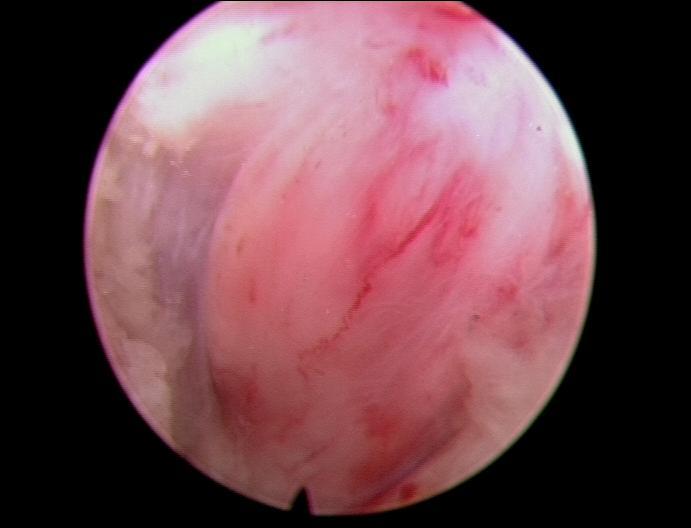

患者颈部及右上肢疼痛麻木,经过数周保守治疗无好转。诊断为神经根型颈椎病,颈56椎间孔狭窄。行颈椎经皮内镜下椎间孔扩大成形术,术后患者疼痛麻木明显好转。